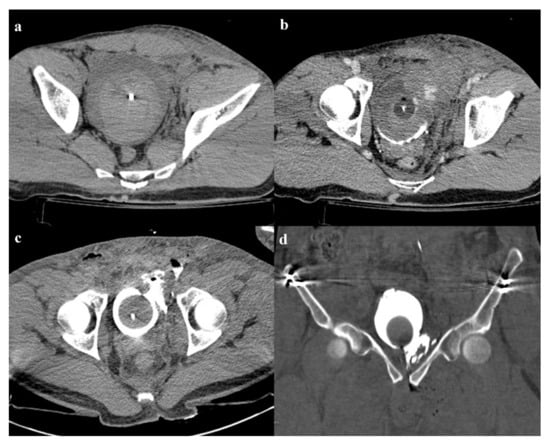

Figure 3. Lateral compression fracture, type 3. Axial CT images show the fracture of the iliac and sacral wings on the left side (a), anterior widening of the right sacroiliac joint (b), and fracture of bilateral pubic branches (c,d).

• Grade 2: grade 1 fractures, iliac wing fracture, posterior sacroiliac joint diastasis (Figure 2). Lateral compression grade 2 injuries have a rotational instability and require a stable internal fixation [3]. In these lesions, an adjunctive temporary external fixation is useful [3].